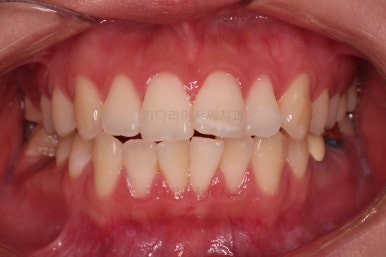

전후 비교 해볼게요.

입안의 모습은 더할나위 없이 잘 개선되었고요.

상하좌우 이 뽑은 위치와 크기가 달라 이정도 중앙선은 매우 잘 맞는 상황인거고요.

얼굴모습도 옆라인이 매우 좋아졌죠.

입이 들어가고 턱선이 살아나게끔 해드렸어요.

임플란트도 안해도 되면서 사랑니까지 잘 사용하고 2년 반 밖에 치료기간도 안걸린 매우 좋은 치료였다고 생각되어집니다.